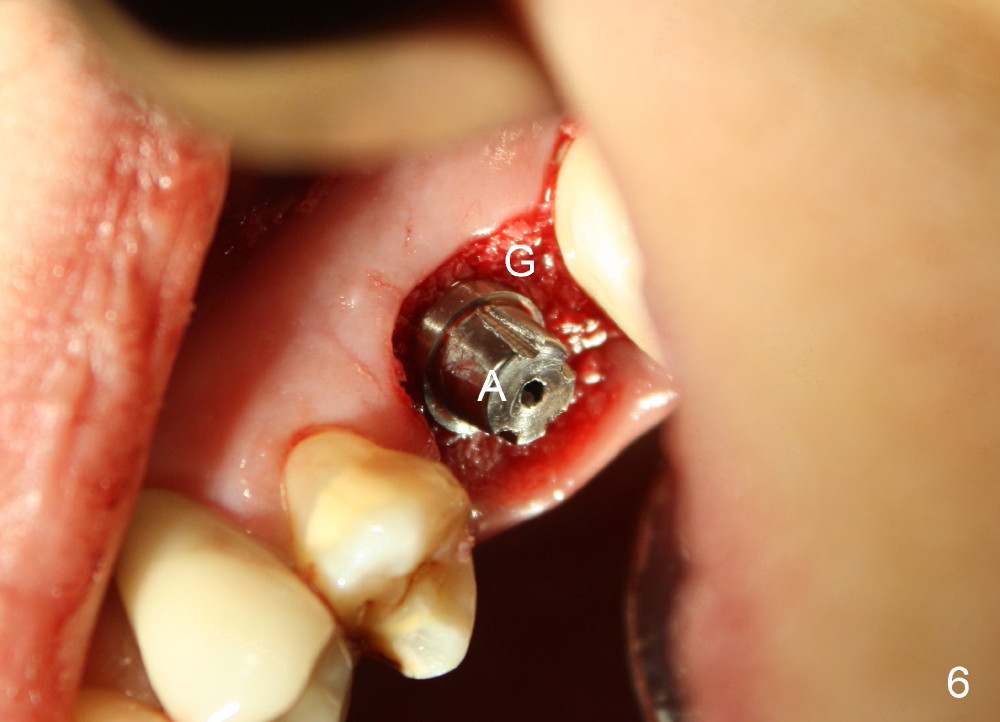

The upper left 1st molar is extracted with sectioning. The septum is large. A surgical fissure bur is used to initiate an osteotomy in the middle of the septum (Fig.1 <; P: palatal socket, MB: mesiobuccal socket), followed by tapping with resistance a 2 mm osteotome ~ 8 mm into the septum. It is tougher to drive 3 mm osteotomy. A 2.5 mm reamer is used to enlarge the osteotomy at 50 RPM at the same depth. Then it is relatively easy to tap 3 and 4 mm osteotomes at ~ 8 mm into the septum. A 4.5x17 mm tap is inserted 8 mm deep with binding to the septum. PA is taken (Fig.2). It appears that the sinus floor (black >) has been penetrated, but the osteotomy has not reached the apex (white >) of the palatal (P) socket. Then the tap is advanced ~ another 3 mm. When the tap is removed, the osteotomy (Fig.3 O) is slightly toward the buccal aspect of the extraction socket, but it has intact wall, including the mesiobuccal (>). The apex of the ostoetomy has no bone, but there is no air leakage. The next tap, 5x17 mm, is inserted shallower (~ 8 mm in the septum; to reduce potential trauma) with stability. However, 6x17 mm tap at the same depth does not obtain stability, since the osteotomy deviates severely mesiobuccally (Fig.4 arrow) with breakdown of the mesiobuccal wall. So the osteotomy has to be deeper in order to achieve stability of 6x17 mm tap (by engaging into more apical bone). A 7x17 mm tap is then intended to be inserted to close the socket as much as possible, but as it is being inserted, the osteotomy is more severely deviated and tilted mesiobuccally with the original mesiobuccal wall further being broken down (not shown). It appears to compromise stability. Mixture of autogenous bone from reamer, allograft and synthetic bone is placed in the mesiobuccal and palatal sockets before placement of the 6x17 mm implant (Fig.5 I). Unfortunately some of graft blocks the apical osteotomy. To clear the blockage, some of previous osteotome and taps are re-inserted. The result is in fact beneficial, as bone graft (G) is pushed upward. Prior to implant placement, nose blowing test does not produce air leakage. More allograft is placed in the coronal portion of the sockets (Fig.6 G); an abutment with precut slots is placed (A) with intention of better holding perio dressing in place after placement of a collagen dressing (Fig.7 M). A temporary crown may be placed when the perio dressing is dislodged. The provisional is to keep the membrane and bone graft in place. The patient returns for follow up 1 week postop. He is symptom free. The abscess appears to be resolving (Fig.8 >); the perio dressing remains in place.